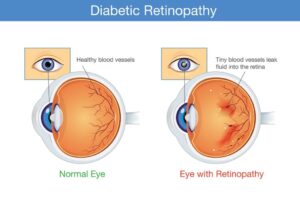

Eye problems:

Some people with diabetes develop an eye disease called diabetic retinopathy which can affect their eyesight. If retinopathy is picked up – usually from an eye screening test – it can be treated and sight loss prevented.